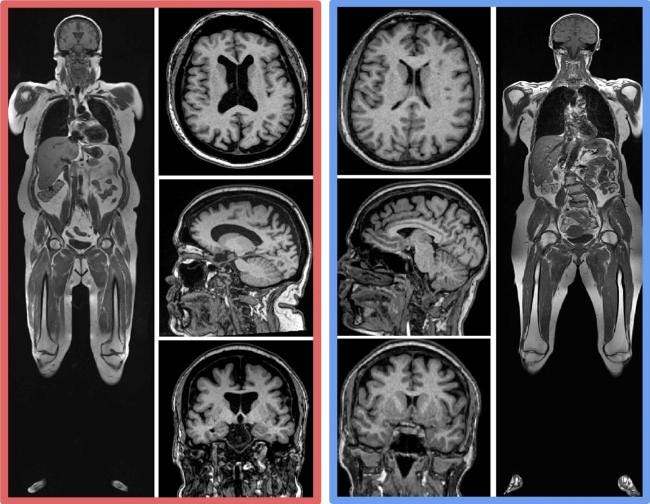

Below is a figure from the study, showing scans of two 61 year old women. The woman on the left has high abdominal fat accumulation, both subcutaneous and visceral (notice the extensive infiltration of fat, which appears white on the scan, into her abdominal cavity). The woman on the right has comparatively little abdominal fat; you'll notice that her fat deposits are concentrated on her hips and thighs, in the typical gynoid fat distribution pattern. Observe the much greater volumes of grey and white matter in the brain of the woman on the right, compared to the larger 'dark' area, indicating brain atrophy, in the woman on the left.